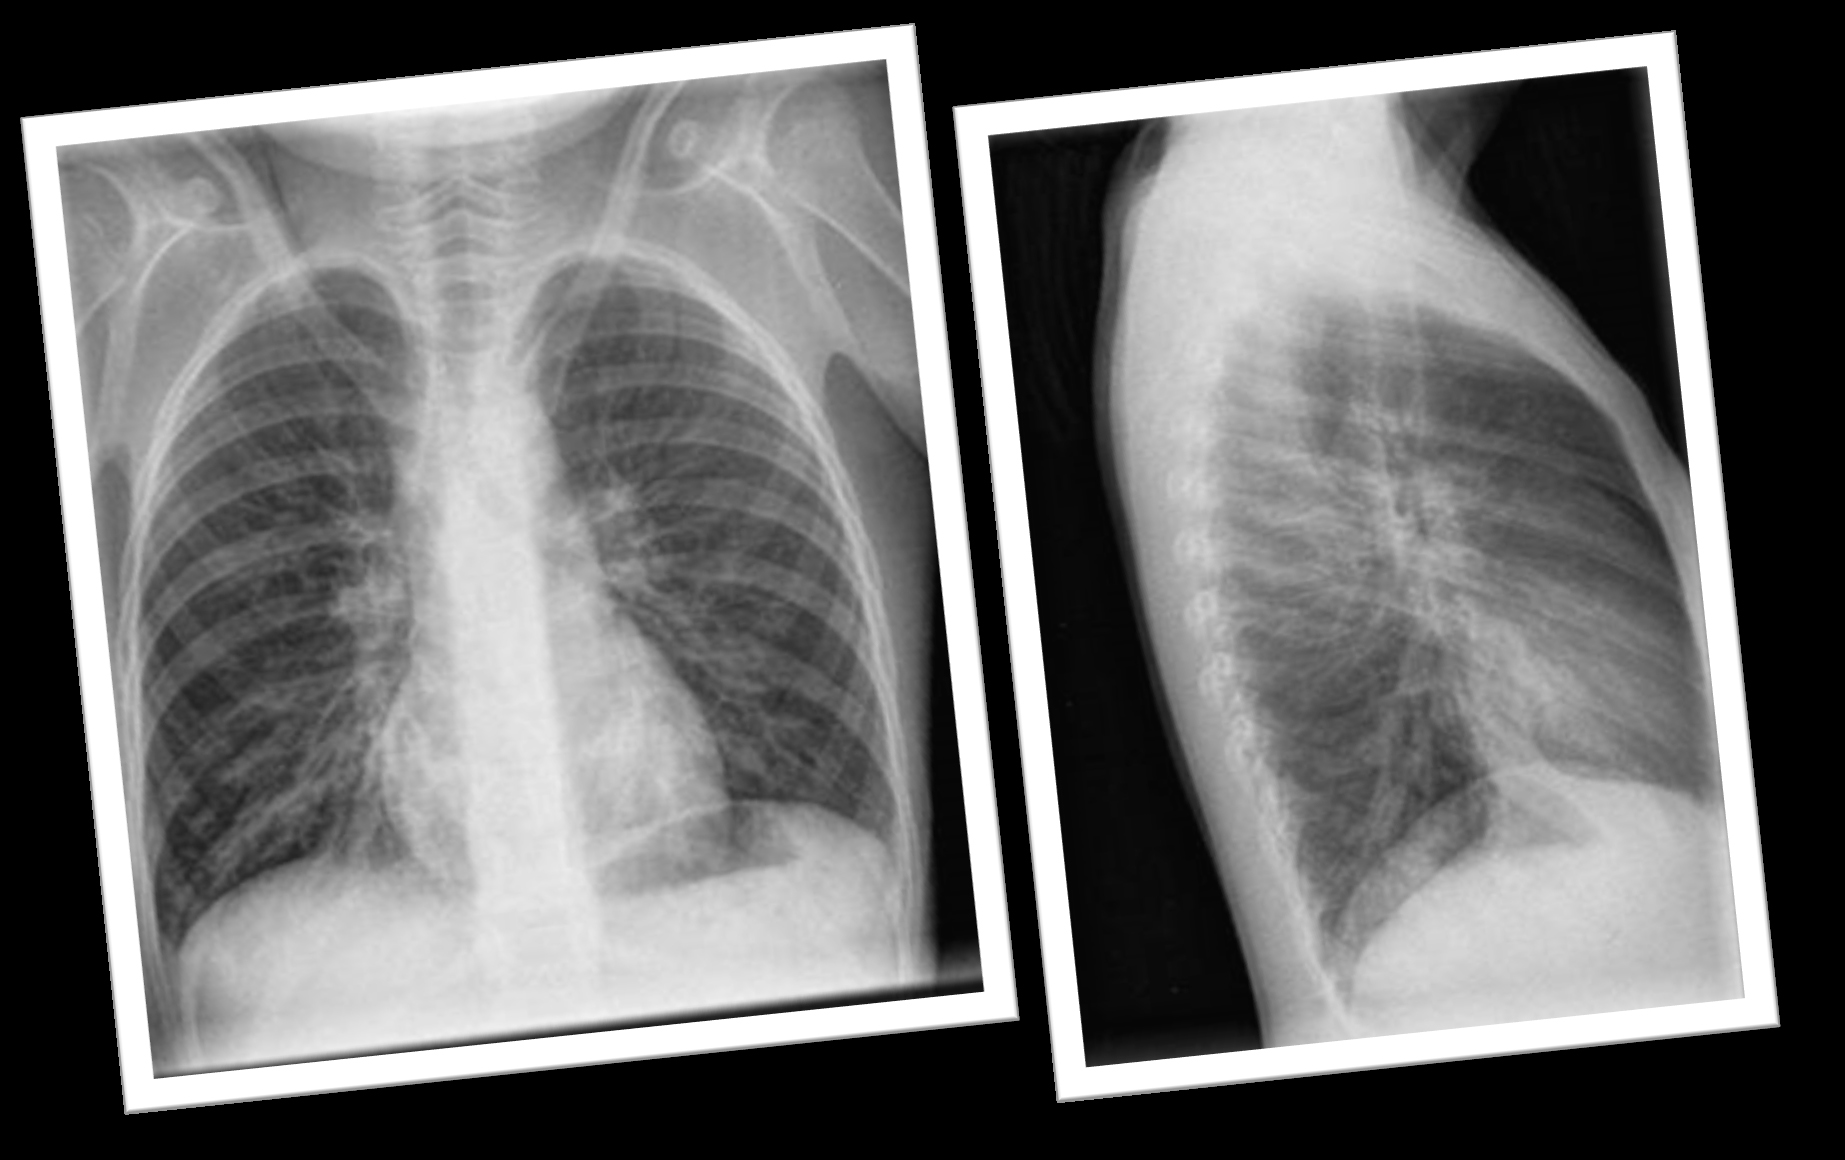

• Radiografía de tórax